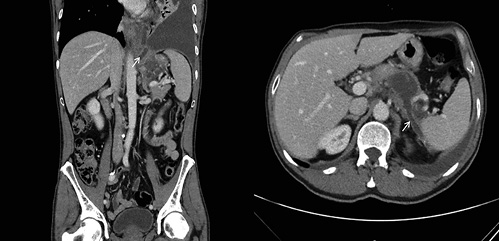

On physical examination, his vital signs were stable and he had no signs of respiratory distress. On pulmonary evaluation, the patient exhibited dullness to percussion and absent breath sounds on the left hemithorax. Blood studies were unremarkable. Chest radiograph showed hypotransparency of the whole left hemithorax (Fig. 1).